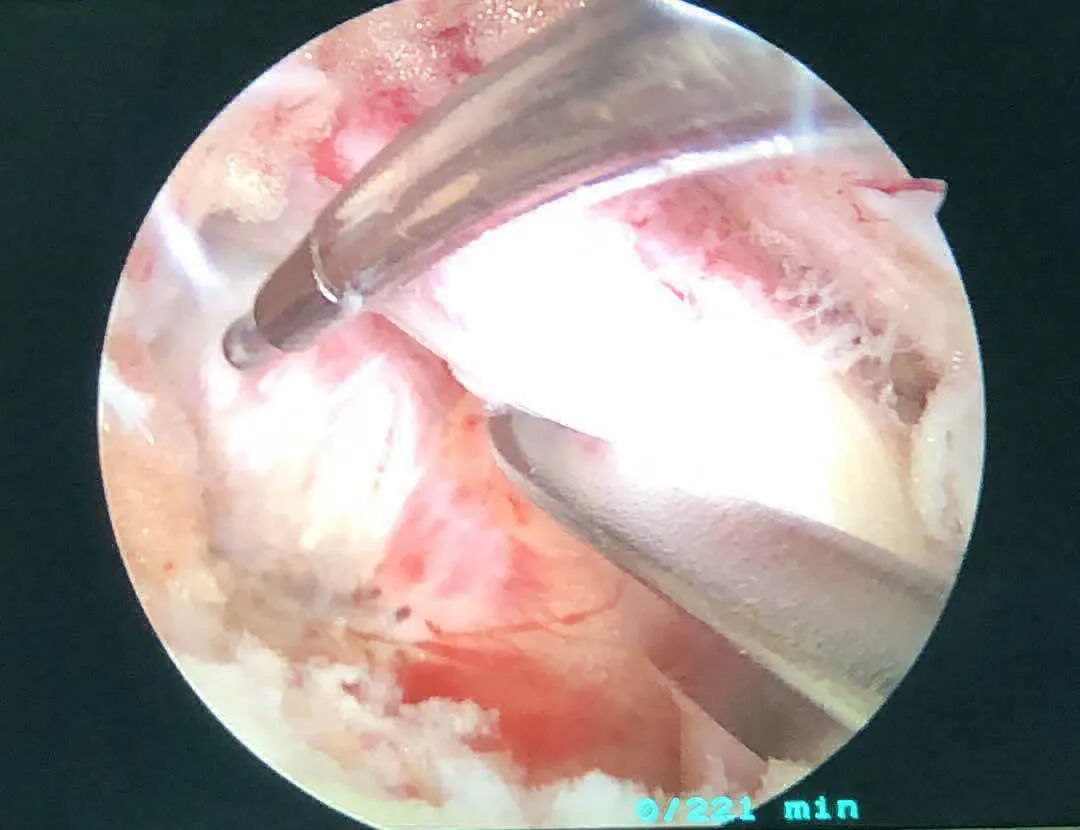

術(shù)中簡(jiǎn)要情況

? ? ?手術(shù)經(jīng)過(guò)、術(shù)中發(fā)現(xiàn)的情況及處理,患 者麻醉成功后取俯臥位,c臂適視確認(rèn)L5/S1間隙左側(cè)觀(guān)察通道及工作通道的體表位置,選擇L5椎板下緣及S1椎板上緣分別作為觀(guān)察通道及工作通道的定位點(diǎn)。常規(guī)消毒鋪巾,貼皮膚保護(hù)膜。沿定位點(diǎn)分別作長(zhǎng)約1cm的縱行切口。置入U(xiǎn)BE肌肉剝離器及內(nèi)窺鏡,透視確認(rèn)雙通道位置及深度滿(mǎn)意。剝離器及擴(kuò)張導(dǎo)管進(jìn)一步將肌內(nèi)從基部分離, 以利于顯露關(guān)節(jié)突面及椎板間間隙。內(nèi)窺鏡下射頻刀頭清理椎板間隙表面肌肉組織,顯露上下椎板,使用椎板咬骨鉗和磨鉆處理椎板邊緣及關(guān)節(jié)突關(guān)節(jié),尋找黃韌帶于椎板破口位置,刮匙將韌帶與椎板邊緣間進(jìn)行修整和分離。使用直骨刀將L5椎板下緣及S1椎板上緣、關(guān)節(jié)突內(nèi)惻緣部分切除行擴(kuò)大處理,進(jìn)一步去除黃韌帶,行側(cè)隱窩減壓處理。剝離神經(jīng)顯露突出的間盤(pán),髓核鉗摘除突出髓核組織,顯露探查見(jiàn)硬膜囊及神經(jīng)根臧壓滿(mǎn)意。鏡下觀(guān)察無(wú)活動(dòng)性出血,神經(jīng)根松弛,滋養(yǎng)血管血運(yùn)恢復(fù),硬膜囊搏動(dòng)好:術(shù)畢徹底止血,退出內(nèi)鏡及工作通道,縫合刀口。手術(shù)順利,麻醉滿(mǎn)意,術(shù)中病人患者生命體征平穩(wěn),無(wú)特殊不適,術(shù)中出血約20ml,術(shù)后安返病房。

術(shù)中圖片

鏡下影像圖片